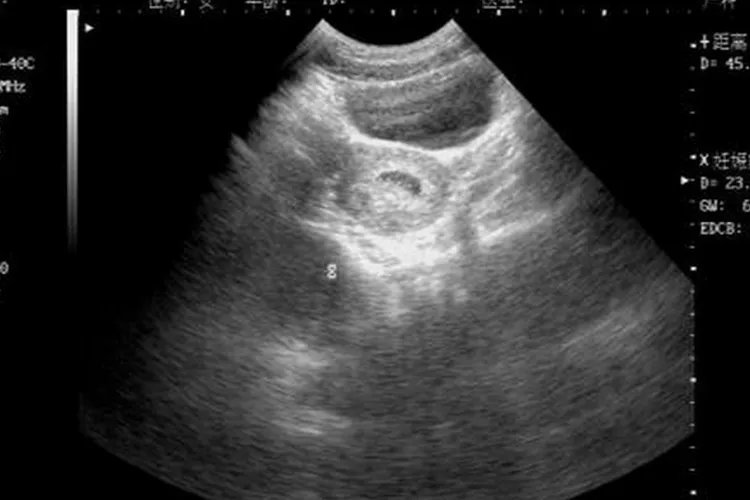

概述怀孕5周时间较短,胎儿尚未成型,宫腔内为圆形或椭圆形的妊娠囊。怀孕5周属于孕早期,此时仍处于较为危险的阶段,需注意加强自身护理。表现怀孕5周时,孕妇宫腔内存在圆形或卵圆形的妊娠囊,胎儿尚未成型,可通过B超观察到。此外孕妇还会出现停经、尿频、乳房胀痛、阴道黏膜和宫颈阴道部充血呈蓝紫色,以及畏寒、头晕、流涎、乏力嗜睡、食欲缺乏、喜食酸物、厌恶油腻、恶心、晨起呕吐等早孕反应。